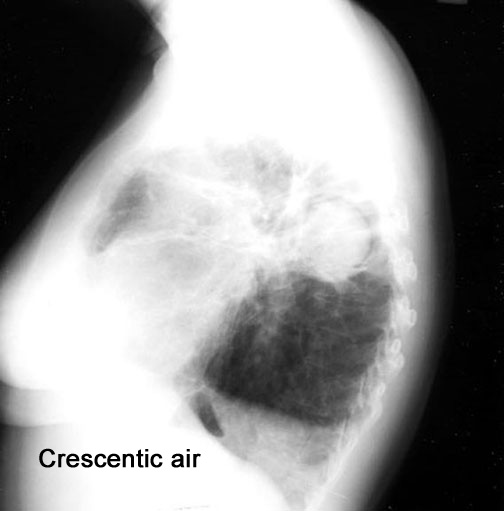

What are the common cavities where fungous ball forms?